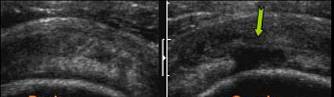

FISURA LONGITUDINALA A BICEPSULUI

FISURA BICEPSULUI →cu epansament lichidian in spatiul de culisare

a m. Confirmare IRM